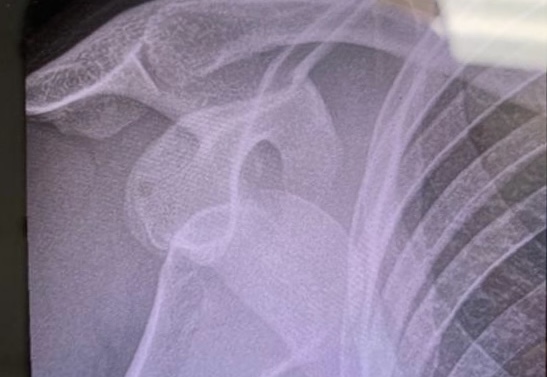

In this week’s podcast Mark and Benji disagree with Hannah over whether Red Bull Hardline belongs in mountain biking, and whether Hannah’s arm belongs in its socket. Or so Mark says. Hannah can’t really remember. They probably talk about rain – has there been anything else to talk about?